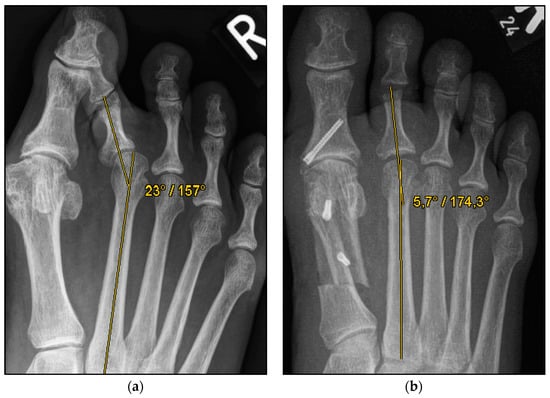

Figure 4.

Pre- and postoperative radiographic results of combined hallux valgus surgery and Weil osteotomy of metatarsal 2 (group A with screw fixation), right foot. (a) Weight-bearing radiograph: anteroposterior view preoperative, (b) weight-bearing radiograph: anteroposterior view, 3 months postoperative.

We collected the following data from the weight-bearing dorsoplantar foot radiographs after a mean follow-up period of 16 weeks (3.6 months). With no significant difference between groups, the mean MTP angle changed from 9.24° to 12.99° preoperative to postoperative (medial deviation: −n, lateral deviation: +n). As can be seen from the mean SEM in Table 2 and Figure 4 and Figure 5, the maximum medial and lateral deviations from pre- to postoperative were significantly different. The mean MTP only changed from 9.3 to 12.9 and was in the range of a mild lateral deviation. This was also observed equally in both groups (p > 0.05). Of note, the postoperative visibility of the joint space was documented significantly more often in the group without screw fixation; this means the space between the subchondral bone of the metatarsal and the toe was seen without overlay (p < 0.05).

The underlying assumption of our study and the knowledge gained from our results can be further elaborated upon. An inharmonious transverse plane alignment can also be corrected with Weil osteotomy and does not require osteosynthetic fixation of the displaced metatarsal head [24]. The results confirm, based on postoperative weight-bearing radiographs, that the surgically induced correction is maintained regardless of screw fixation. An objectifiable criterion was the metatarsophalangeal angle measured pre- and postoperatively using weight-bearing radiographs in the dorsoplantar view (Figure 1 and Figure 2). In both treatment groups, it was possible to bring the maximum axis deviation closer to the mean value; the mean difference between pre- and postoperative metatarsophalangeal angle was only 3.8°. On average, 10.6 degrees were required to achieve the desired surgical result, regardless of screw fixation (Figure 4 and Figure 5). However, the significantly higher possibility of viewing the affected metatarsal joint space postoperatively can also be considered a successful outcome of the restoration without screw fixation. The visibility of the articular surface, in turn, proves the centering of the metatarsal head in the transverse plane as well as a sufficient correction in the sagittal plane (Figure 6 and Figure 7) [25]. Again, the inability to view the joint space indicates that inadequate correction of the claw toe deformity as well as the metatarsal, which was considered “too long”, was performed [1,14,26].